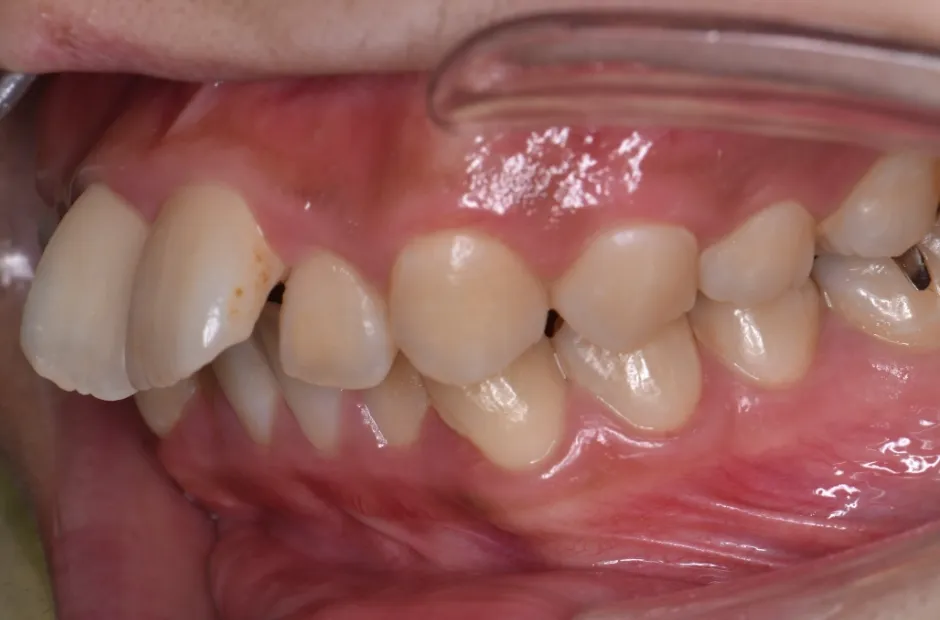

| 診断名・主訴 | 下顎前突、叢生 |

|---|---|

| 年齢・性別 | 23歳・女性 |

| 治療期間・回数 | 3年 |

| 治療に用いた主な装置 | 上顎5,5 下顎4,4 |

| 抜歯部位 | 舌側矯正 |

| 治療費 | 100万円(税抜) |

| リスク・副作用 | 装置による違和感・疼痛・歯肉退縮・歯根吸収・虫歯のリスクなど |

治療前